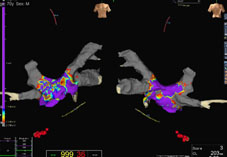

3D定位系統影像示意圖

3D立體定位在複雜性心律不整影像示意圖

心房顫動3D 立體定位系統輔助示意圖

冷凍消融術3D立體定位系統影像示意圖